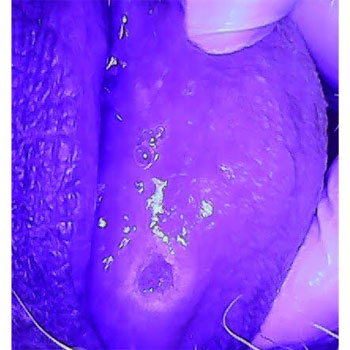

CASE OF LICHEN PLANUS

CLINICAL IMAGE

FILTERED IMAGE

BLUE LIGHT IMAGE

BLUE LIGHT IMAGE FILTERED